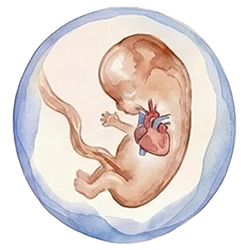

Expert Scan at around 12-13 weeks is essential to exclude severe physical anomalies

A second visit is usually arranged once the NIPT results are back, typically around 12–13 weeks. At this stage, a more detailed early anomaly scan is performed, with particular attention to the baby’s heart and other organs, and the findings from both the scan and the NIPT are reviewed together. If the NIPT result is high chance, and/or the fetus has persistent increased NT or structural anomalies, the options for invasive diagnostic testing (CVS or amniocentesis) are then discussed.